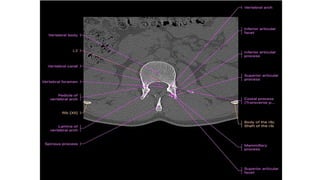

VERTEBRAL CANAL

• The spinal cord lies within a bony canal formed by adjacent vertebrae

and soft tissue elements, the vertebral canal.

• Anterior wall: the vertebral bodies of the vertebrae, intervertebral

discs, and associated ligaments,

• Lateral walls and roof: the vertebral arches and ligaments.

VERTEBRAL CANAL • Thespinal cord lies within a bony canal formed by adjacent vertebrae and soft tissue elements, the vertebral canal. • Anterior wall: the vertebral bodies of the vertebrae, intervertebral discs, and associated ligaments, • Lateral walls and roof: the vertebral arches and ligaments.